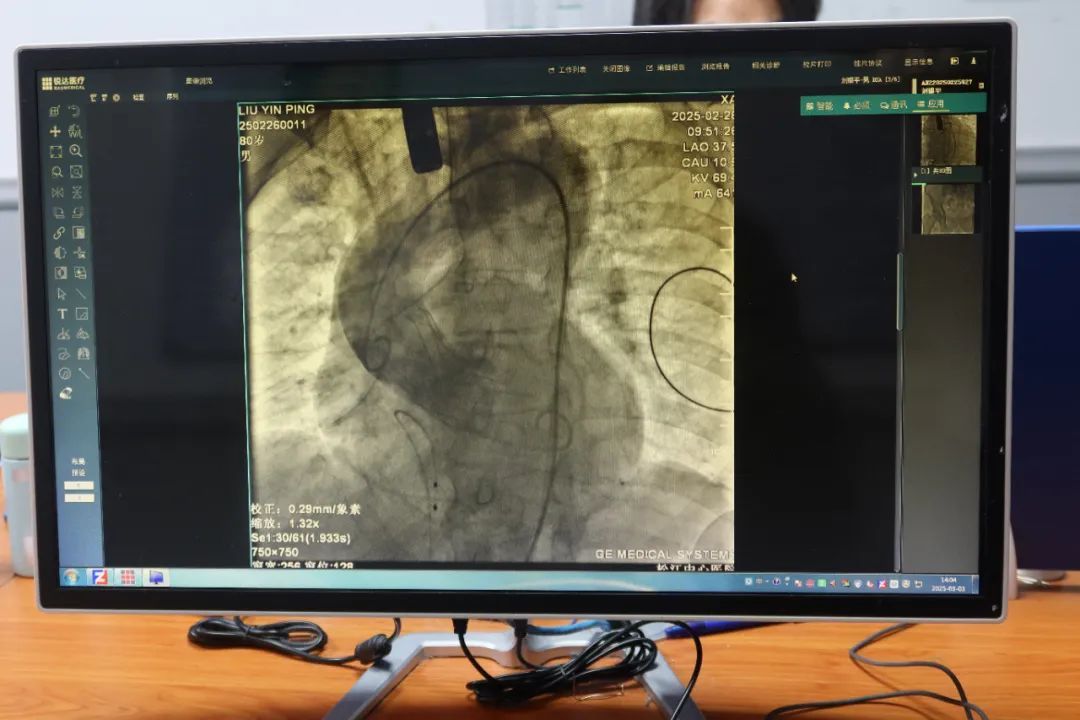

心内科主任侯磊检查后发现,老人的症状源于主动脉瓣严重狭窄。考虑到患者年近八旬,团队决定采用创伤极小的TAVR技术。TAVR是一种微创技术,无需开胸,就能为心脏更换“大门”。如果把心脏比作一栋房子,主动脉瓣就是心脏向全身供血的“大门”。当这扇“门”因老化或病变无法正常开合时,患者会出现胸闷、头晕甚至猝死。

“传统开胸手术创伤大、风险高,许多高龄患者难以承受。”侯磊介绍说,“而TAVR手术不需要动手术刀,只需在腿部血管穿刺,通过导管将折叠的人工瓣膜送到心脏位置,像‘撑伞’一样展开替换病变瓣膜。”这种手术无需心脏停跳,患者术后第二天就能下床活动。

手术当天,松江医院心内科团队在复旦大学附属中山医院专家周达新、张晓春教授的指导下,仅仅一个小时就顺利完成手术。术后刘老伯胸闷、头晕等症状立即消失,次日便恢复自主活动。“手术后第三天他就能自己走路,现在都不需要我们特别照顾了。”刘老伯家属说。良好的手术效果远远超出全家预期,患者家属特别送上锦旗表示感谢。